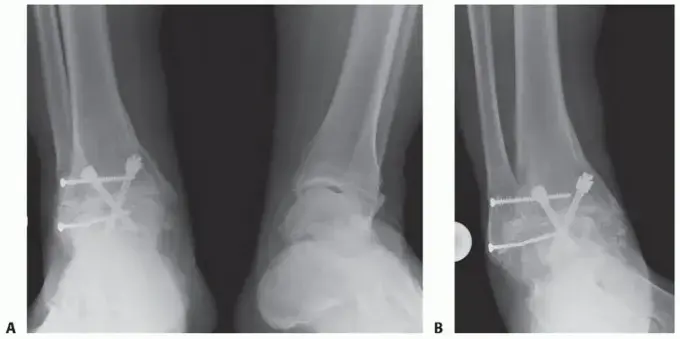

استخدام المسمار النخاعي (Intramedullary Nail)

• ما هو المسمار النخاعي؟ هو قضيب معدني طويل وقوي يتم إدخاله في تجويف العظم (نخاع العظم) الذي يمتد عبر عظمة الساق (Tibia) نزولاً عبر عظم الكاحل (Talus) وصولاً إلى عظم العقب (Calcaneus).

• لماذا يستخدم؟ يوفر هذا المسمار تثبيتاً داخلياً قوياً ومستقراً جداً للعظام المدمجة. يسمح للعظام بالالتئام معاً بمرور الوقت، مما يضمن دمجاً صلباً وناجحاً. يُعرف الأستاذ الدكتور محمد هطيف بخبرته في اختيار وتطبيق أفضل أنواع المسامير النخاعية وتقنيات الدمج لضمان أفضل النتائج لمرضاه.